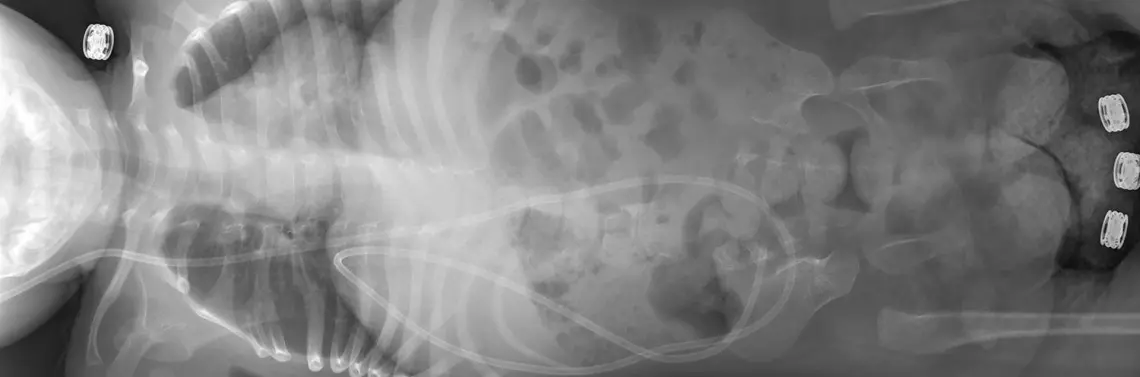

Przepuklina oponowo-rdzeniowa w Polsce występuje rocznie z częstością ok. 1000 przypadków. Wada ta powstaje w życiu płodowym, jest zaburzeniem formowania się struktur rdzenia kręgowego i kręgosłupa i lokalizuje się na przebiegu całej długości kręgosłupa (zdj. 1). Etiologia wad cewy nerwowej nie jest jednoznaczna. Czynniki powodujące jej powstawanie są: genetyczne, uzależnione od czynników środowiskowych, takich jak niedobór witamin A i E, niedobór kwasu foliowego, niedobór kwasu pantotenowego, niedotlenienie, infekcje wirusowe, promieniowanie jonizujące i chemioterapeutyki.